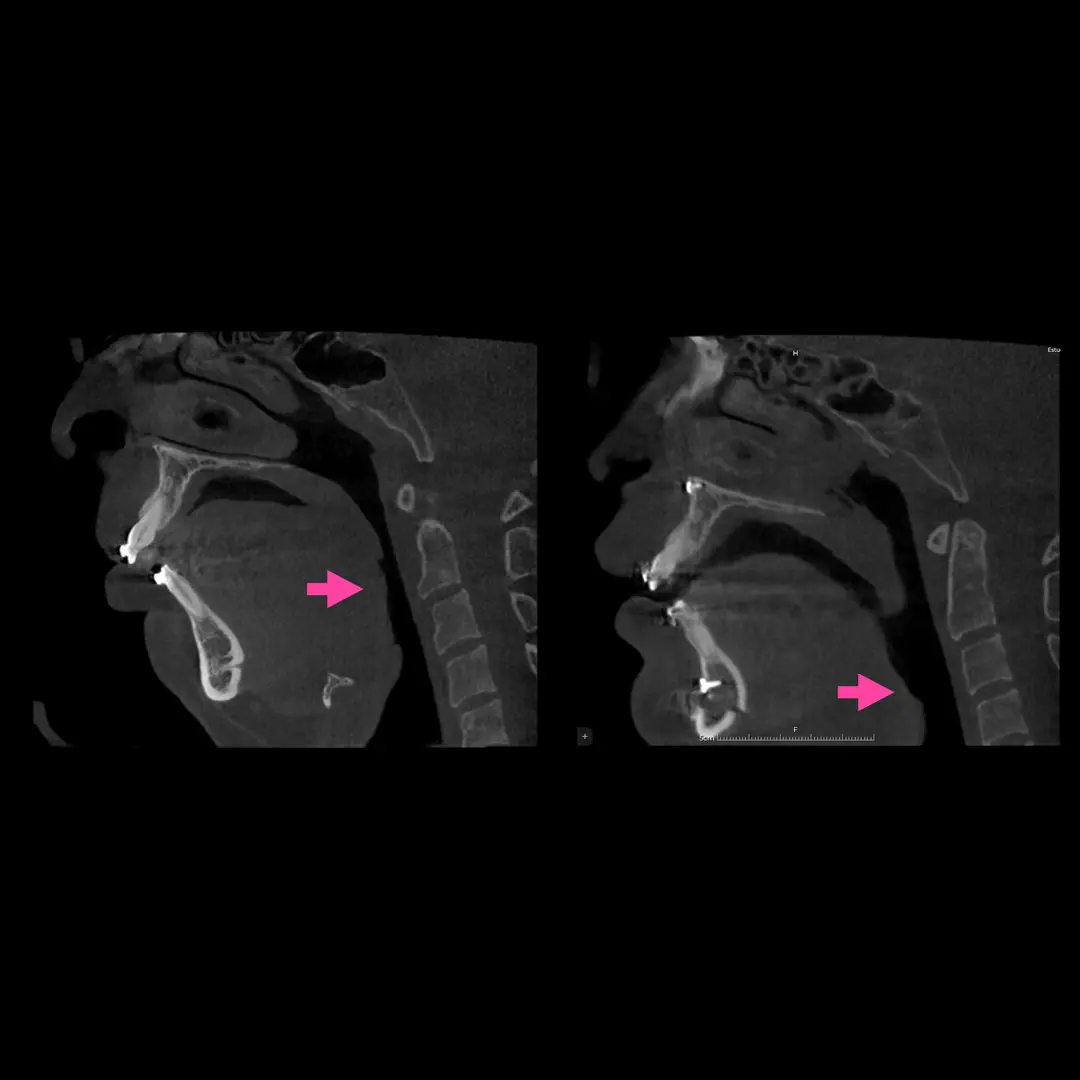

Cirugía ortognática (asimetrías faciales)

Corrección quirúrgica de deformidades óseas en mandíbula y maxilares para mejorar estética, mordida y respiración.

La cirugía ortognática, del griego orthos, «recto» y gnathos, «mandíbula», es una intervención quirúrgica que se encarga de corregir las deformidades dento-craneo-maxilofaciales mediante movimientos óseos maxilares y mandibulares, para lograr el equilibrio perfecto entre todas las características faciales del paciente.

Este tipo de alteraciones faciales aparecen en la fase de crecimiento de los pacientes, se estabilizan al final de la misma, y pueden causar problemas como apnea del sueño, trastornos de la ATM, problemas de maloclusión o falta de armonía esquelética, entre otros.